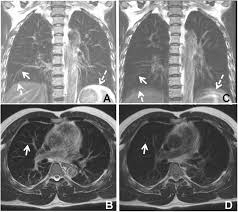

Multimodality Imaging In Connective Tissue Disease Related Interstitial Lung Disease Clinical Radiology